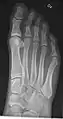

- پا / انگشتان پا - Dorsoplantar، مایل و جانبی[18]

پا راست نرمال به وسیله پروجکشن dorsoplantar

پروجکشن مایل

پروجکشن جانبی